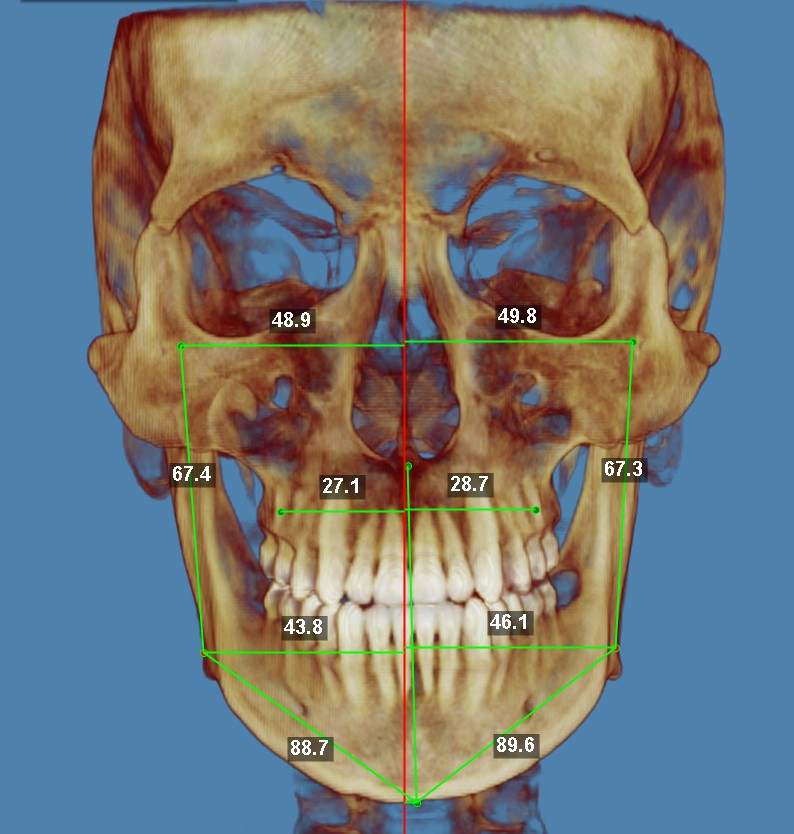

фронтальный расчёт.jpg

23 года, мезиальный прикус, 3 класс

ну и самое ебаное, на верхней челюсти зубы стоят в 2 ряда

а вот пик 4 - ещё хуже, тут видно, что верхняя челюсть уже нижней на 2мм, что то значит? а это значит, что надо пилить без вариантов!